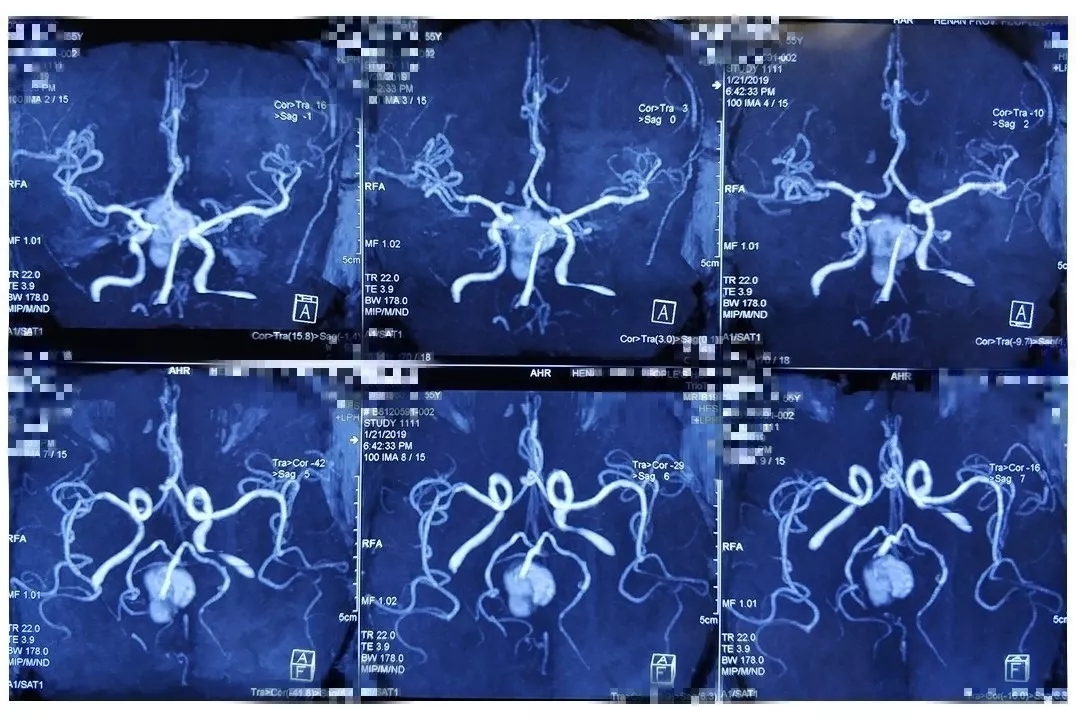

入院后完善CTA,DSA等检查提示颅内多发动脉瘤:

其中右侧颈内动脉眼段动脉瘤(约13.8*14mm大小,瘤颈8.04mm)。和家属沟通病情,告知介入和开颅手术两种治疗方式的风险利弊后,患者家属选择开颅右侧眼动脉段动脉瘤夹闭手术治疗。

进一步行DSA+CT融合,模拟手术入路视角。